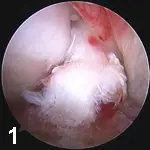

Stifle JointIn our practices, the stifle is the most commonly "scoped" joint. Typical indications include diagnosis and treatment of cruciate ligament disease (Figure 1), meniscal injury  (Figures 2A and B), and osteochondritis dissecans (OCD). Arthroscopy provides magnification, access, and fluid distention, allowing a more thorough evaluation of the stifle joint than with

arthrotomy. Damaged cranial cruciate ligaments can be accurately debrided with small power-driven shavers. Meniscal tears can be identified and treated with partial meniscectomy or, in some cases, repaired OCD lesions can be debrided and autogenous osteochondral grafts placed via arthroscopy.